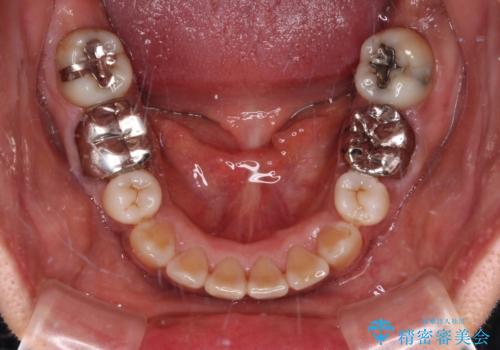

抜歯矯正により口元が引っ込みすぎて、ほうれい線が顕著となるのではないかと心配しておりましたが、矯正後にほうれい線が気になることはなく、口元もすっきりとした感じになりました。